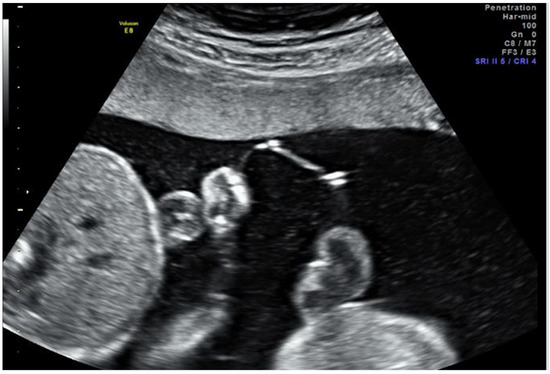

Figure 1.

Ultrasound image the day after fetoscopic laser photocoagulation (FLP) showing the intervening membranes with a small defect, fluid equilibration between sacs, and similar fluid echogenicity between sacs.